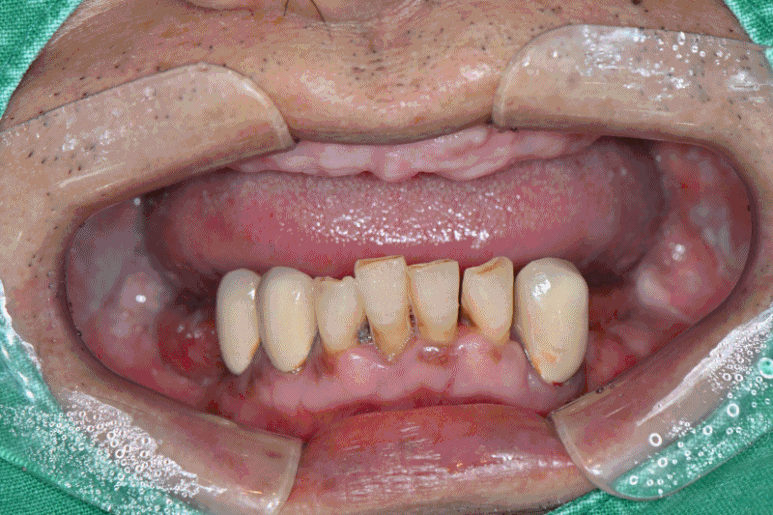

풀아치 임플란트 본원 사례

실제로는 오히려 적게 심는 방식입니다.

4~6개의 임플란트로 상악 또는 하악 전체를 안정적으로 고정하는 구조인데요.

그렇기 때문에 오히려 더욱 정밀한 분석과 진료가 진행되어야 합니다.

입 안 공간, 잇몸의 형태, 얼굴의 입체감까지 고려해서 임플란트 위치를 잡아야..

말할 때나 웃을 때 어색함 없이 자연스럽죠.